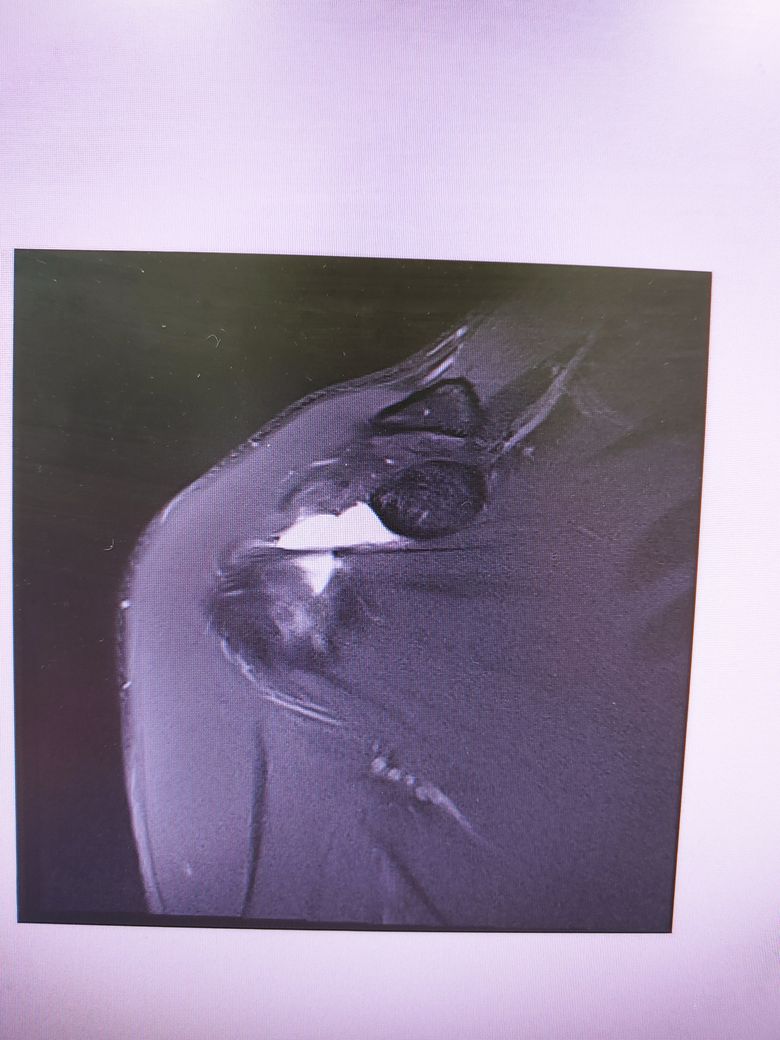

어깨 mri 판독 가능할런지요?

족구 중 다른 사람과 부딛혀 넘어지는데

상대가 넘어지지 말라고 팔을 잡아주었습니다.

그런데 무방비 상태에서 팔이 당기다보니

어깨에서 소리가나더라구요.

세달째 통증이 지속되어

병원가서 Mri는 찍고 아직 진단은 받지 못했습니다..

회전근개 부분파열으로 볼 수 있나요..?

어깨 MRI는 수십장 이상의 사진이 연속적으로 찍히는 것으로 위 사진들만으로는 정확한 판별이 어렵겠습니다.

나와있는 cut에는 큰 문제가 없어보입니다.

현재 사진상으로 회전근개 파열을 확실히 진단하기는 힘들것 같습니다.

하지만 현재 MRI상 어깨 관절내에 밝게 보이는 곳은 물 또는 혈액등으로, 활액막염 등으로 인해 염증성 변화가 일어난 것으로 보입니다.

이는 소염진통제 등을 드시면서 경과관찰을 해보시는 것이 좋겠으며, 현재 사진만으로는 회전근개 파열을 단정하기 어려우므로 정확한 진단에 대해서는 해당병원에서 설명을 들으시는 것이 좋겠습니다.